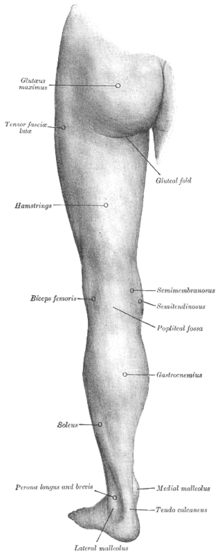

Membre inférieur (anatomie humaine)

Les membres inférieurs chez l'Homme sont les membres de la locomotion, permettant aux humains de se soutenir et de se déplacer d'un endroit à un autre en marchant.

Les membres inférieurs sont formés de six parties ou régions principales :

- La partie supérieure s'appelle la région glutéale, située entre le bassin et la cuisse.

- La région fémorale (la cuisse), située entre la hanche et la région du genou.

- La région du genou, située entre la cuisse et la jambe.

- La région crurale (la jambe), située entre le genou et la cheville.

- La région talo-crurale (la cheville ou cou-de-pied), située entre le pied et la jambe.

- La partie inférieure s'appelle la région du pied.

Muscles

- De la cuisse

- De la jambe

- Du pied